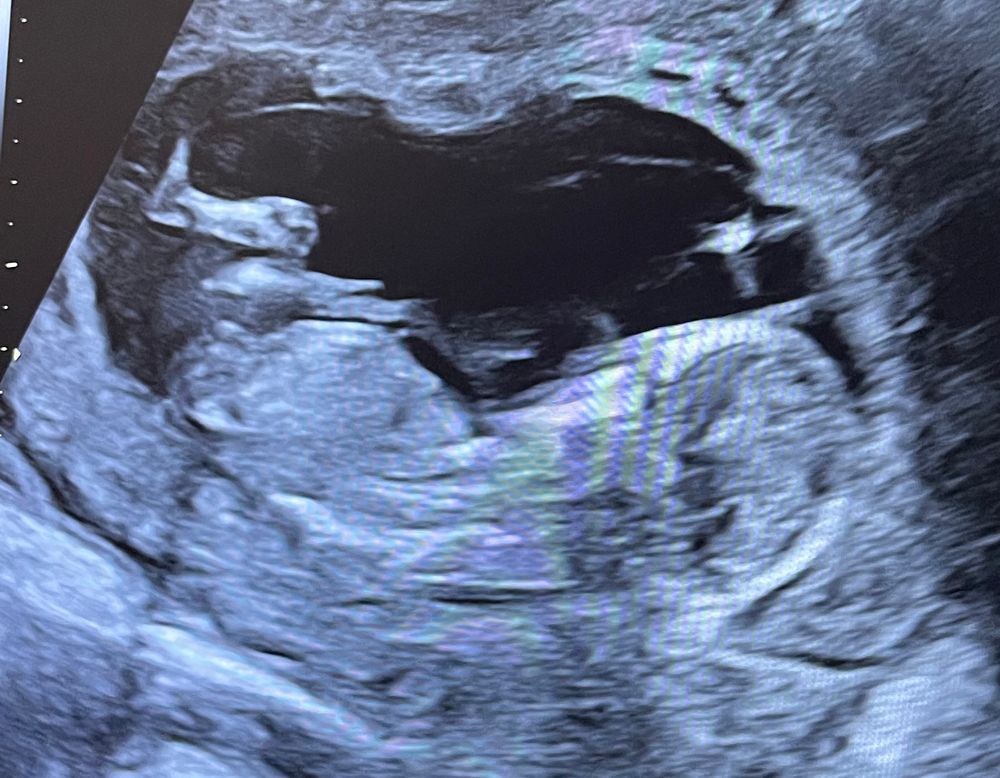

Пол ребенка в 13 недель

Анютка, скажите, пожалуйста, вы видете половой бугорок? Который торчит вверх рядом с пуповиной, этот?

Айсо, мне кажется бугорок за ножкой, ниже))

Посмотрите в интернете как определить пол ребенка по узи, мне кажется девочка)

Ксения , врач сказал, дождаться 2 ого скрининга или после 16 недель. Просто интересно может по фото кто то может определить